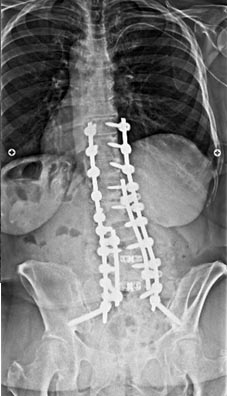

67 year old woman with Parkininsons presenting with neuromuscular kyphoscoliosis with inability to stand and look upright. Patient expressed that she was tired of talking to other people’s belly buttons.

T2 to sacrum/pelvis spinal fusion. Patient is pain free and able to stand upright and walk normally for the first time in years.